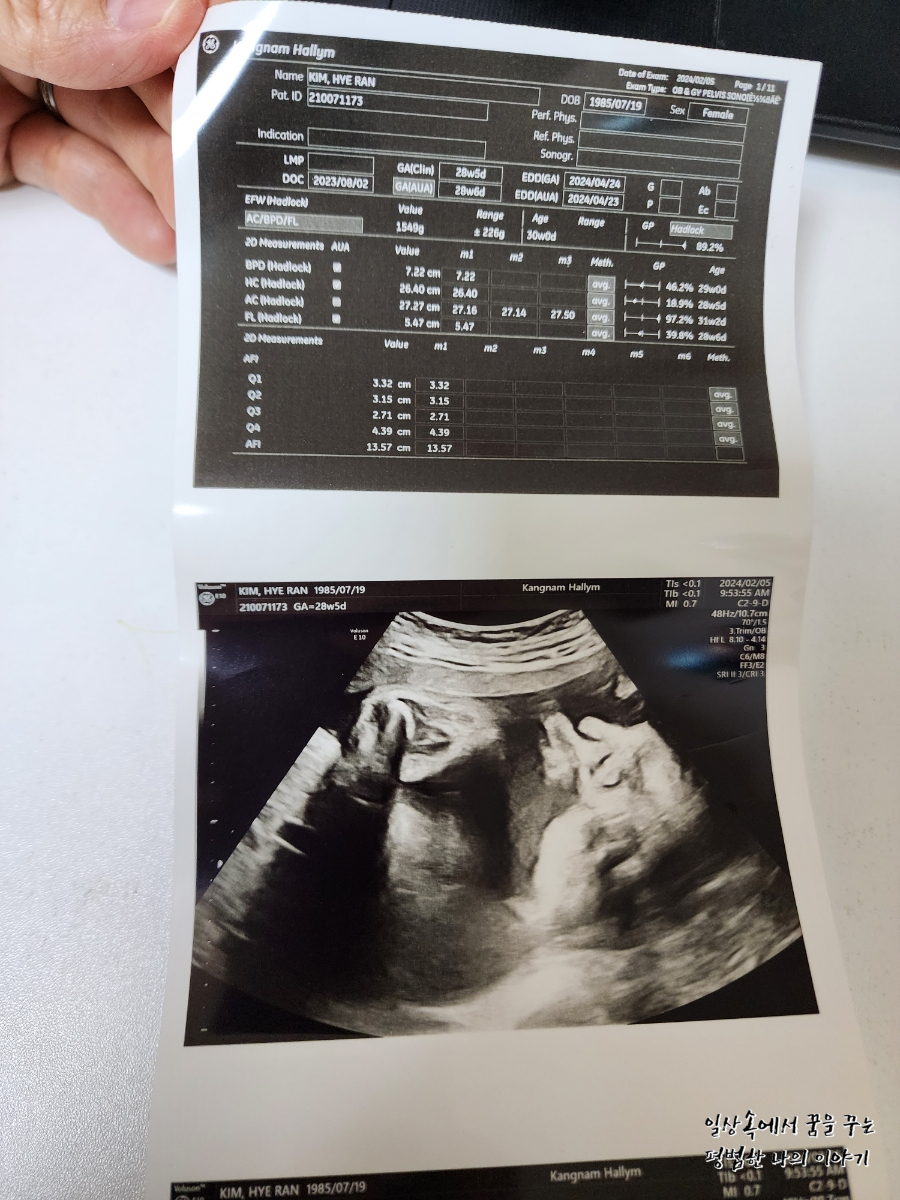

2024년 2월 5일(월요일)

BPD(Biparietal Diameter, 위에서 볼 때 태아 머리 단면의 가장 긴 길이): 7.22cm

HC(Head Circumference, 태아 머리둘레): 26.4cm

AC(Abdominal Circumference, 배 둘레): 27.27cm

EDD(Expected Date of Delivery, 출산 예정일): 2024년 4월 24일

FL(Femur Length, 허벅지뼈 길이): 5.47cm

GA(Gestational Age, 임신 주차): 28주 차 5일

EFW(Estimated Fatal Weight, 태아 예상 체중)=EBW(Estimated Body Weight): 1571g

FHR(Fetal Heart Rate, 심장박동 수): 143bpm

CL(Cervical Length, 자궁경부 길이): 정상

AF(Amniotic Fluid, 양수): 정상